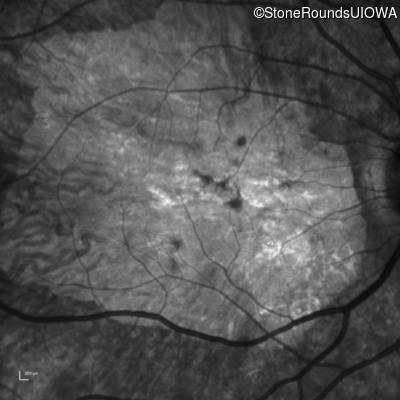

Infrared Fundus Photograph - Right - 20/250 sc

Exemplar